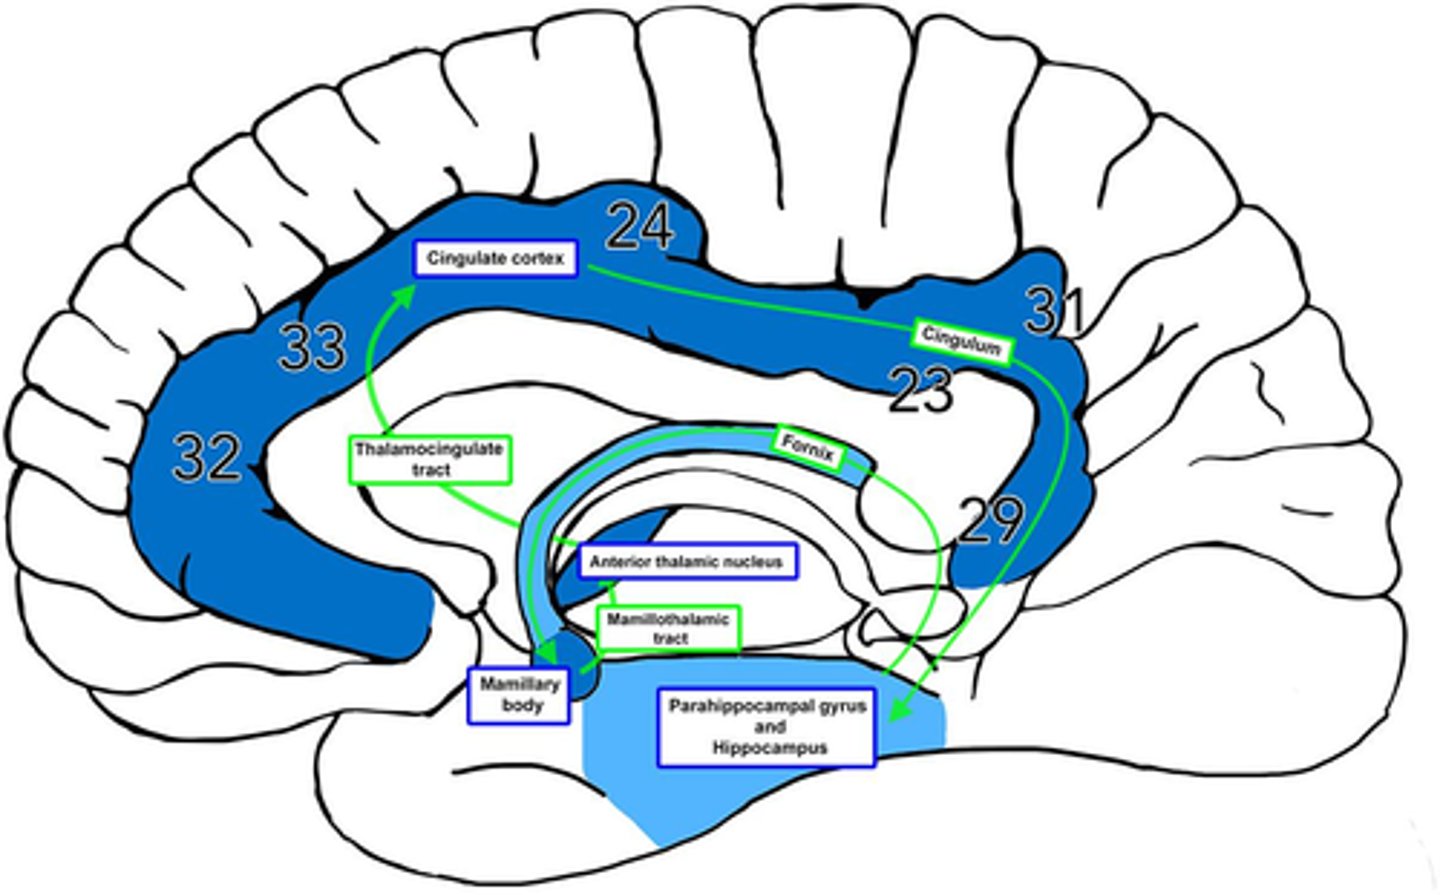

What is efferent to the anterior nuclei of the thalamus?

hippocampus via the cingulum

What is afferent to the anterior nuclei of the thalamus?

hippocampus and hypothalamus via mammillothalamic tract

What is the pathway from the hippocampus to the anterior nuclei of the thalamus?

1. hippocampus

2. fornix

3. mammillary nuclei

4. mammillothalamic tract

5. anterior nuclei (thalamus)

Where does the cingulate gyrus run?

superior to the corpus callosum